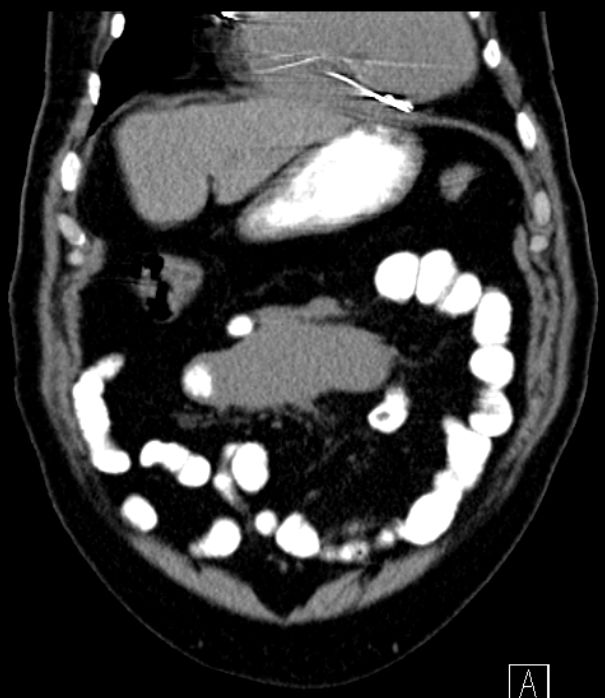

Mesenteriale LK |

68-jährige Frau mit Völlegefühl und

Heißhungerattacken seit 8 Monaten. LSK mit Lymphknotenbiopsie: Atypische

Follikelformationen mit CD20, CD10 und BCL2-Expression.![]() | |||